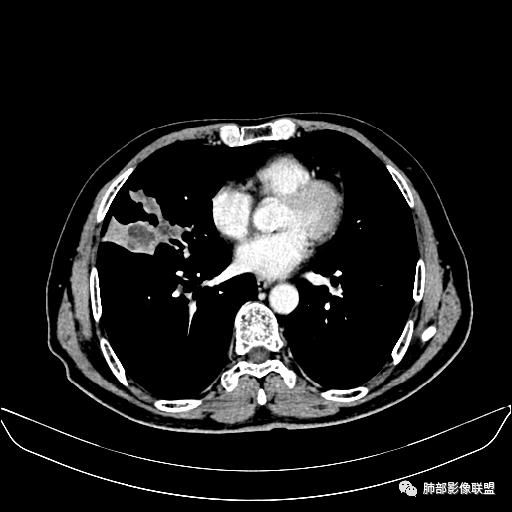

住院4天后行胸部增强CT

动脉期

静脉期

老年男性,因“咳嗽咳痰1月余。”入院。病程中咳嗽咳痰,咳黄白痰,间断咯少许鲜红色痰血。PPD阳性。胸CT:右肺中叶外侧段支气管管腔阻塞,大片实性病变,病灶边缘光滑,部分边缘膨隆,可见分叶,肺门及纵隔可见肿大淋巴结,并可见钙化。增强可见病灶明显强化,而且延迟强化明显,病灶内多发低密度区,内见血管影,血管变细、部分血管破坏。考虑恶性病变可能性大,鉴别慢性肉芽肿性病变。

右肺中叶外侧段管腔阻塞、实性病变,病灶边缘光滑,可见分叶,肺门及纵隔可见肿大淋巴结,并可见钙化。增强可见病灶内多发低密度区。

胸CT:跨叶大肿块,主体在中叶,右中叶外侧段支气管阻塞,病灶部分边缘膨隆,可见分叶,部分边缘平直,肺门及纵隔可见肿大淋巴结。增强病灶不均匀强化,延迟强化明显,病灶内多发低密度区,内见血管飘浮,部分血管变细、模糊。考虑:恶性病变可能性大,大细胞?淋巴瘤?鉴别慢性肉芽肿性病变。

右肺中叶软组织肿块,外围向内生长,叶间胸膜向前内移位,肿块近肺门侧跨叶,中叶外侧段支气管截断,密度不均匀,双侧肺门及隆突下见肿大淋巴结,增强后呈中度不均质强化,肺动脉供血,多发坏死区,边界尚清,坏死区域内见结构,结合病史考虑恶性,鉴别诊断1结核,爬行征是沿支气管树分布,外宽,内窄,周围有卫星灶,内气管狭窄后扩张,此例沿叶间胸膜长轴分布,气管有截断,不典型。2炎性肉芽肿,符合的地方下方层面增强后延迟性轻度环形强化,不符临床无发热等急性感染病史,实验室指标不符,病灶周围渗出及慢性炎性改变有,不明显。